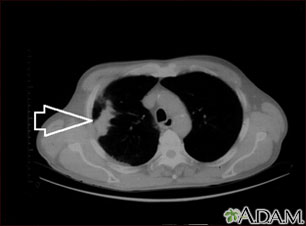

This is a CT scan of the upper chest showing a mass in the right lung (seen on the left side of the picture).